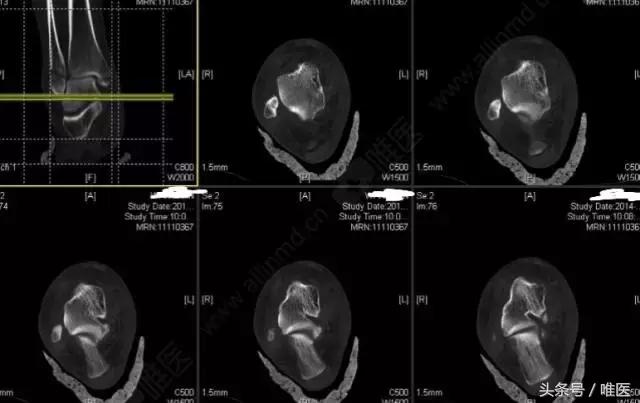

CT二维重建: 右侧踝关节骨折

L-H分型:旋后外旋型 IV度;

Danis-Webber分型:B型

治疗前影像